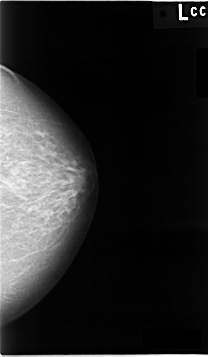

C_0010_1.LEFT_CC

LEFT_CC LINES 4632 PIXELS_PER_LINE 2696 BITS_PER_PIXEL 12 RESOLUTION 50 NON_OVERLAY